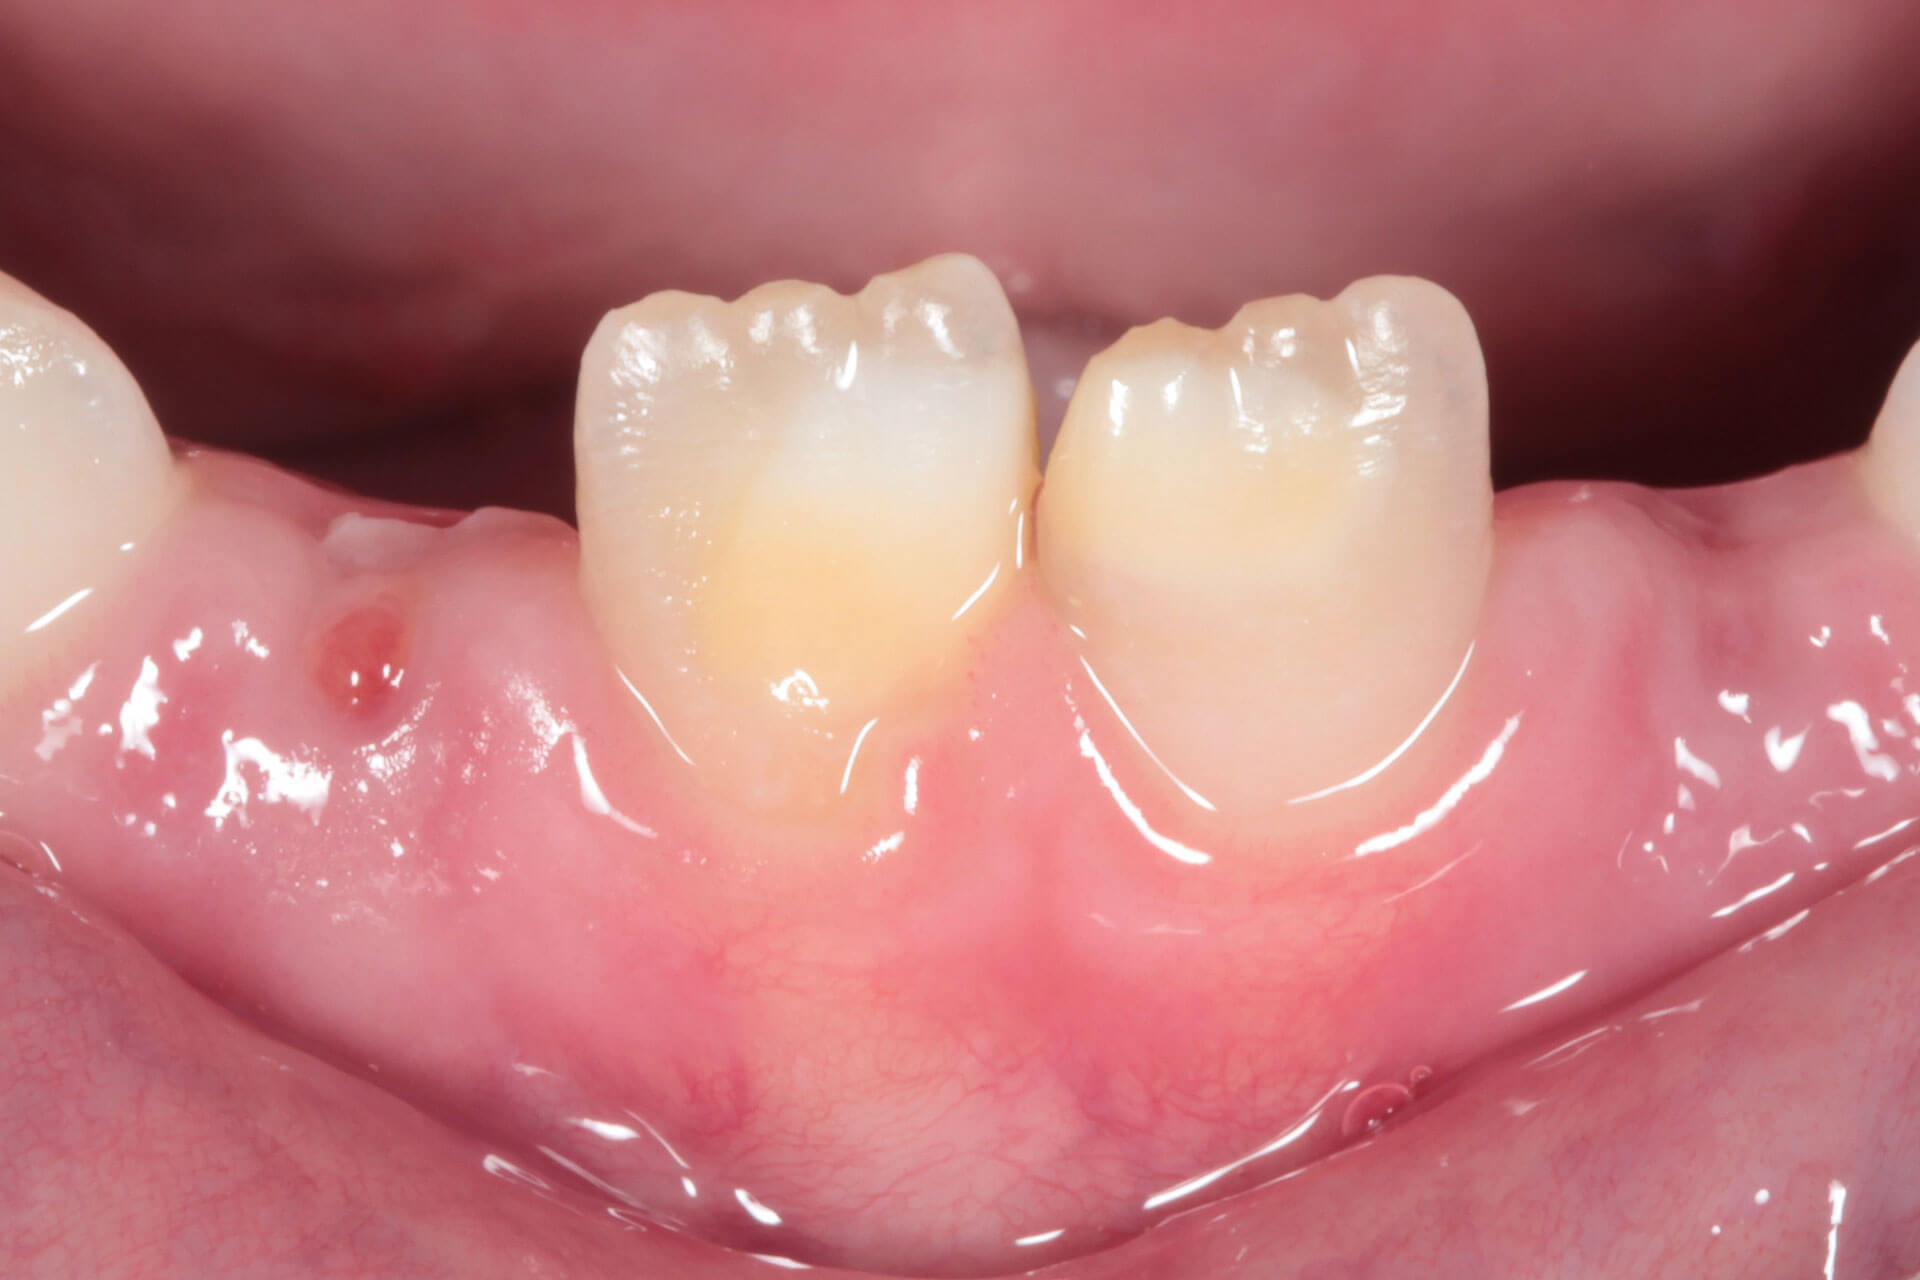

PARODONTOLOGIA

Per la tua salute orale ma non solo.

La malattia parodontale, infatti, ti espone maggiormente al rischio di malattie cardiovascolari, diabete, complicanze in gravidanza.

- Diagnosi precoce di gengivite, parodontite e dei loro fattori predisponenti

- Terapia chirurgica per l’eliminazione e/o la riduzione delle tasche

- Terapia chirurgica plastica e rigenerativa dei tessuti parodontali e peri-implantari